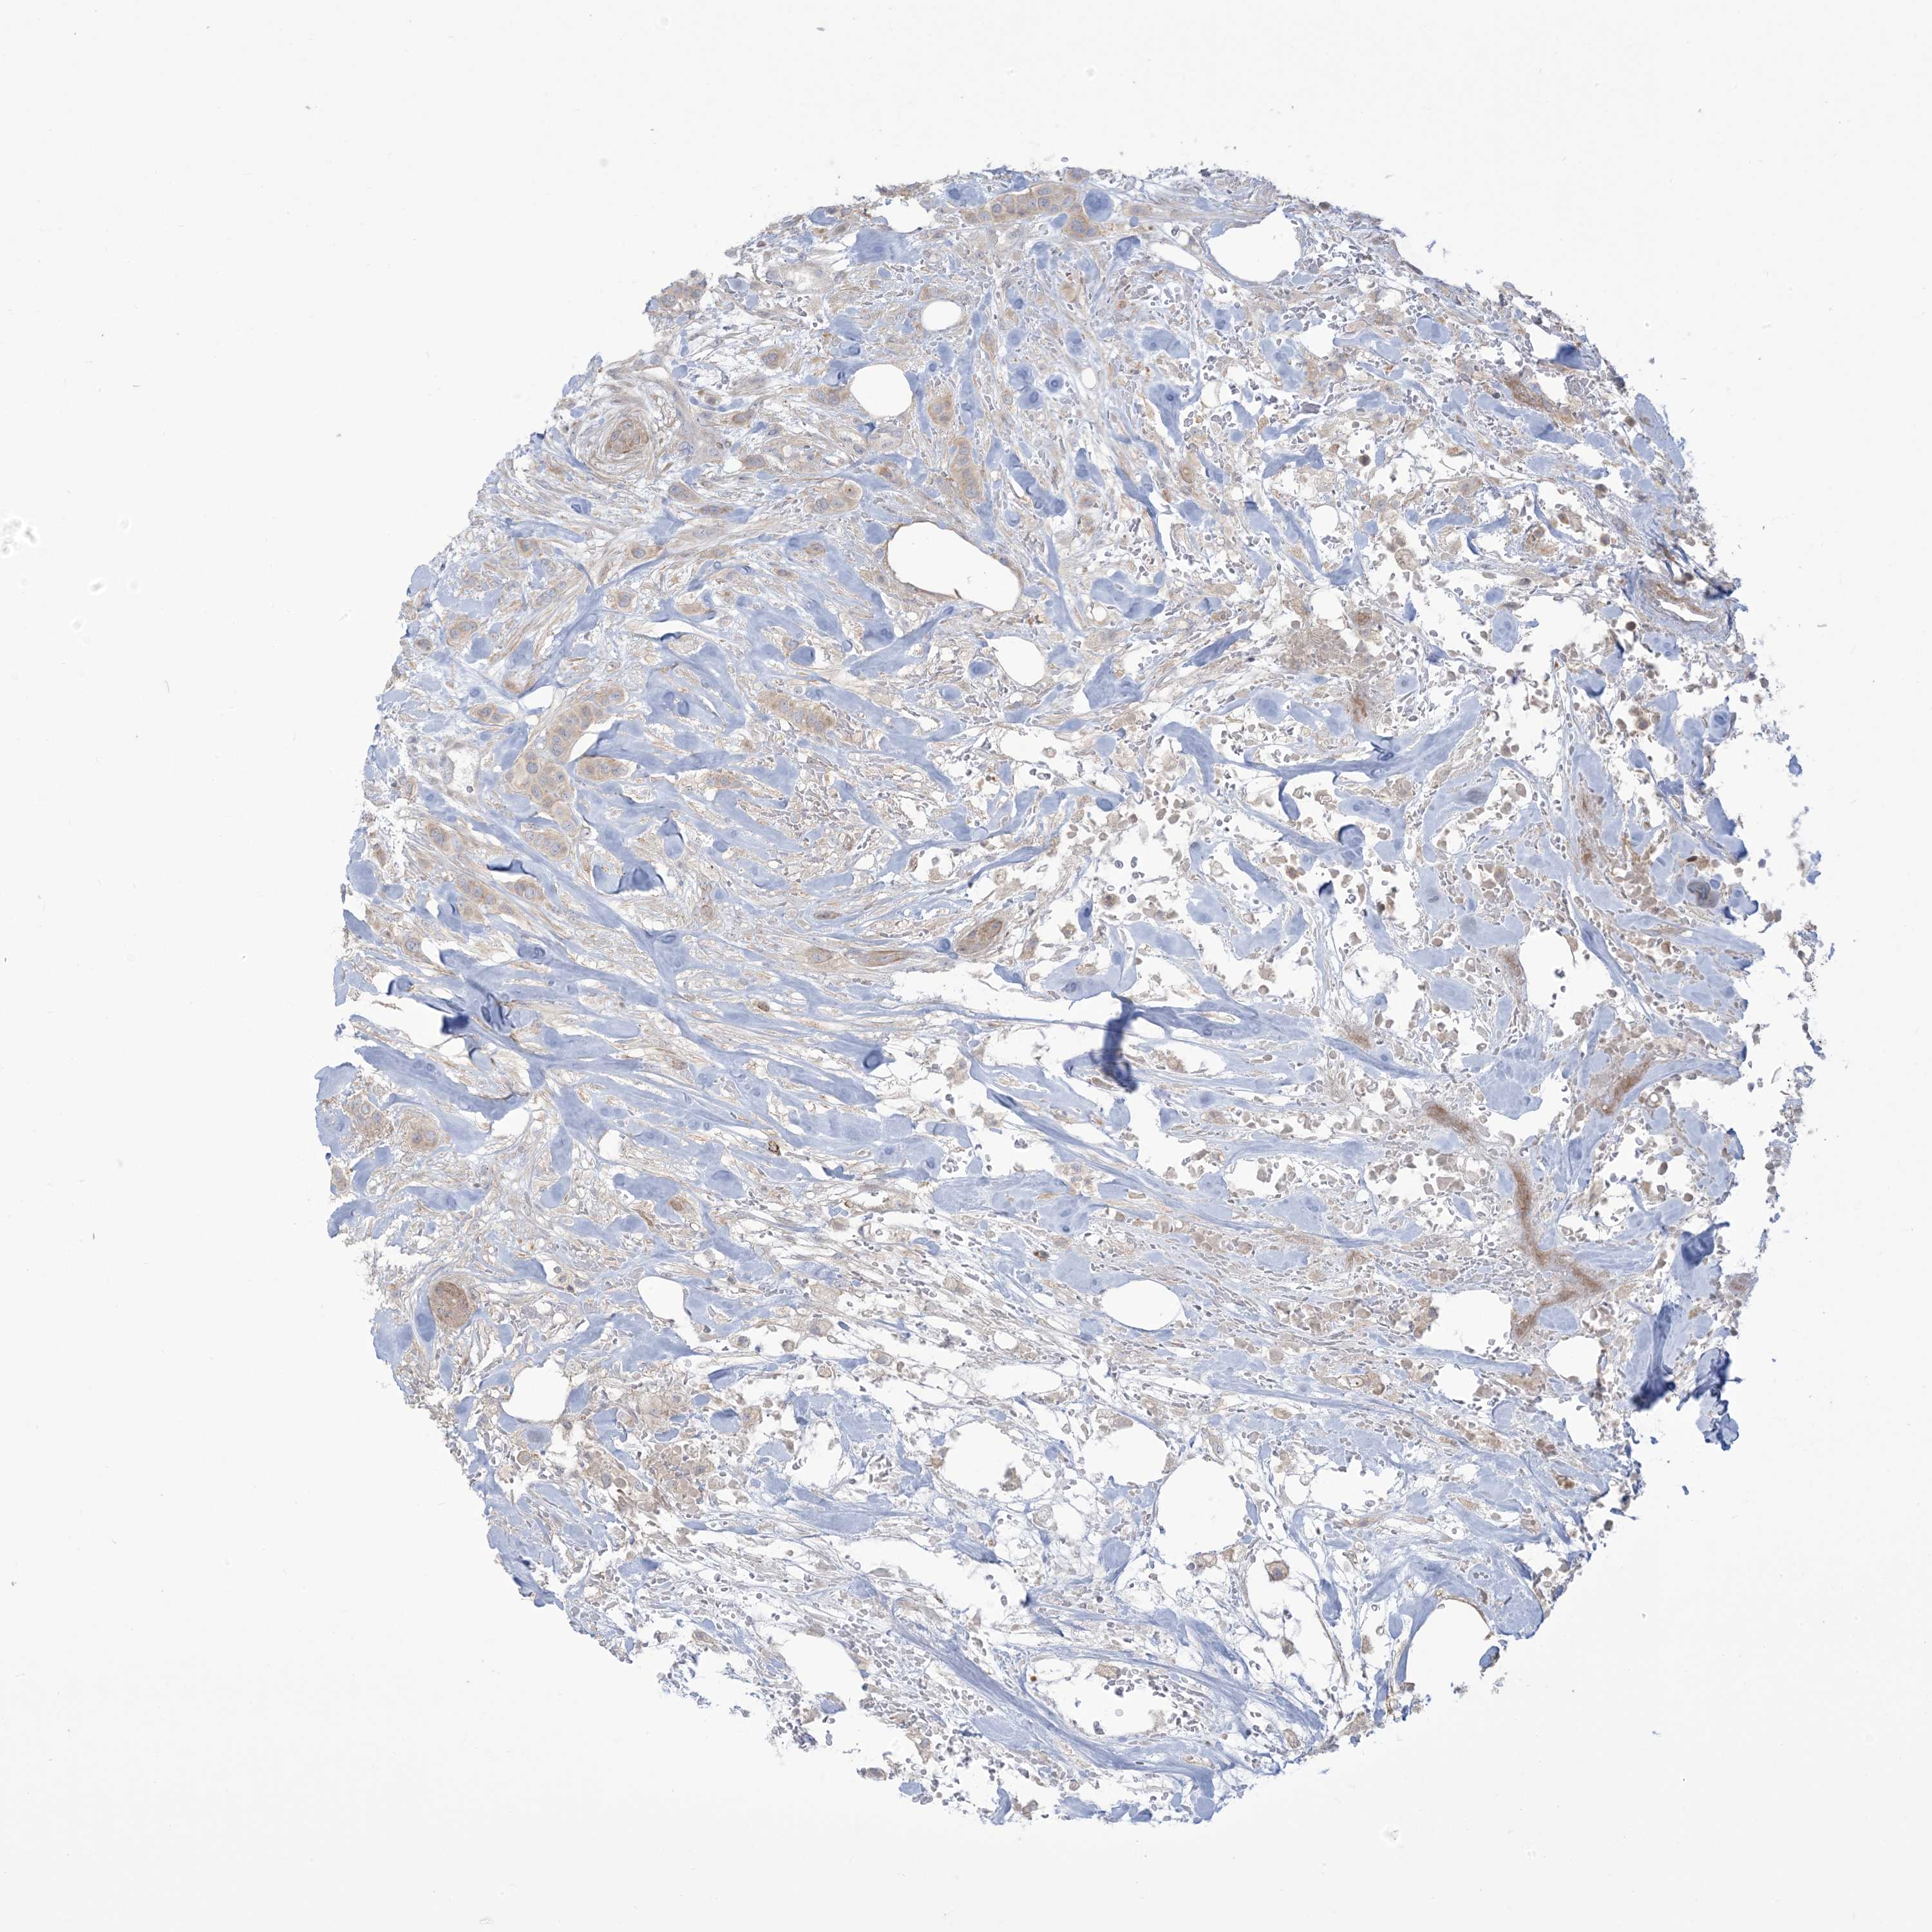

CANCER BREAST CANCER Show tissue menu

BRCA TCGA BRCA VALIDATION PROTEIN EXPRESSION